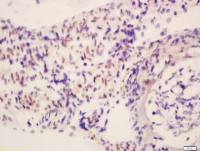

| 产品应用 | Flow-Cyt=1:50-200 IF=1:50-200 not yet tested in other applications. optimal dilutions/concentrations should be determined by the end user. |